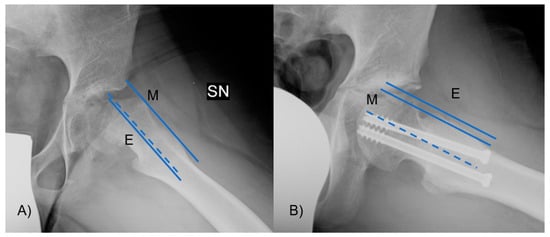

The epiphyseal–metaphyseal offset was assessed in the frog-leg lateral view by determining the disparity between a line traced along the front border of the epiphysis, parallel to the femoral neck, and a line traced along the proximal–anterior edge of the metaphysis, also parallel to the femoral neck (Figure 5). A negative value means that the epiphysis lies posteriorly to the metaphysis. Finally, the presence of AVN or cartilage degeneration was evaluated at the latest available follow-up.

Figure 5.

The epiphyseal–metaphyseal offset was measured in the frog-leg lateral view as the difference between (E) a line drawn along the anterior edge of the epiphysis, parallel to the femoral neck, and (M) a line drawn along the proximal–anterior edge of the metaphysis, also parallel to the femoral neck. In figure (A) the offset is reduced due to the head slippage, while (B) after the reduction it is improved.

Preoperatively, 7 out of 24 patients were evaluated as grave cases (29%) and 17 were evaluated as mild (71%); the slippage in the preoperative period was 44.3° (35–53° range). After surgery, there was an average slippage of 12.2° (range, 8–17°) (p = 0.033). The initial lateral α angle measured at 94° (range, 62–113°) on the radiographs before the operation, and the subsequent average postoperative angle was 47.5° (range, 42–55°) (p = 0.02). Preoperatively, the–metaphyseal offset averaged −3.3 mm (range, −6.2 to −0.4 mm), and postoperatively, it was 0.24 mm (range, −1.5 to 1.2 mm) (p = 0.01). Degenerative changes were absent in 20 hips and mild in 3 hips, and 1 hip showed significant morphological alterations at the femoral head due to AVN.